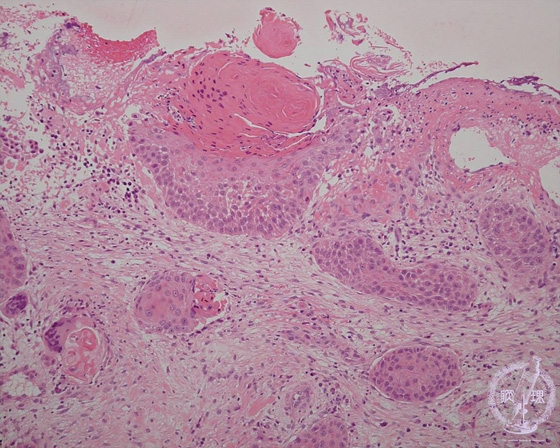

• š(8)Squamous cell carcinoma(invasive)

Squamous cell carcinomas arise from squamous cells of the skin. In this case, the tumor shows dermal invasion.